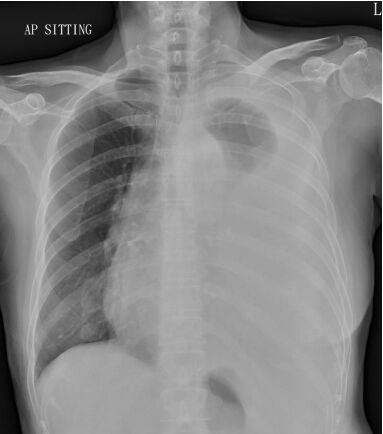

21. 黃先生68歲,有慢性阻塞性肺病(chronic obstructive pulmonary disease, COPD)的病史。因為發燒三天,合併呼吸急促與咳嗽有黃濃痰的狀況來到急診。黃先生自訴三個月前曾經因為慢性阻塞性肺病急性發 作(COPD exacerbation)住院一週,使用過類固醇與注射型抗生素。於急診時理學檢查發現呼吸急促,意識清楚。體溫 38.6°C, 心跳110 /minute, 血壓 136/80 mm Hg, 呼吸速率 26 /minute, 不使用氧氣的情況下SPO2: 91%,CXR如圖所示。WBC: 12,000 /mm³, platelet count: 159,000 per /mm³, BUN 26 mg /dl, creatinine 1.2 mg/dl。於急診的處置下列何者不適當?